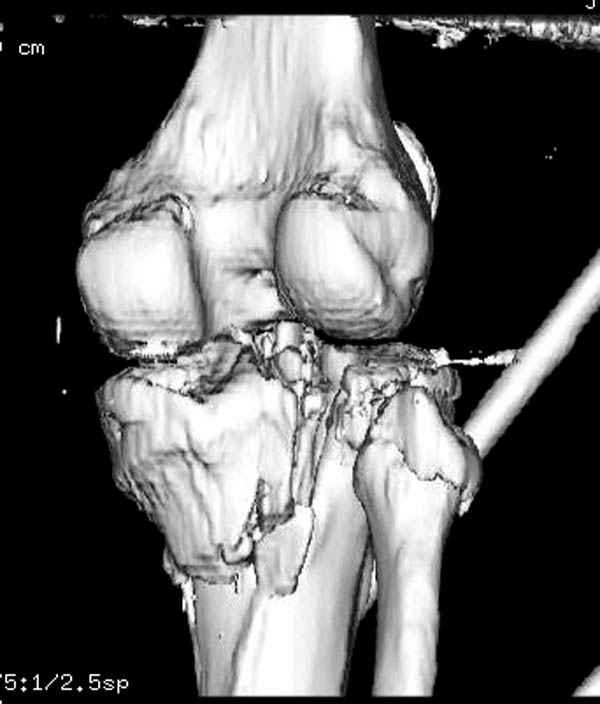

Интрамедуллярный остеосинтез диафизарного перелома тут возможен, но в первую очередь надо с помощью КТ уточнить повреждение суставного конца. Импрессионный перелом наружного мыщелка явный есть, может, и медиальная колонна повреждена, так что надо в первую очередь планировать открытую репозицию с замещением дефекта с фиксацией пластиной или аппаратом. Если получается технически, можно поверх уже синтезированного стержнем диафиза.

Пациенту сделали КТ - ухитрились сделать на шине Белера (не давал положить прямую ногу) - срезали передний отдел. Планируется на пятницу (24.12) на операцию - синтез длинной мыщелковой LCP-пластиной Synthes :). Отек ближе к слову умеренный (окружность голени +4 см по сравнению со здоровой). КТ и снимок на вытяжении прилагаются.

На представленных предоперационных срезах КТ огромный задне-медиальный фрагмент расположен больше кзади, чем медиально. Для планирования, кроме поперечных срезов, надо ориентироваться на корональные срезы, которые укажут топографию верхушки медиального фрагмента.